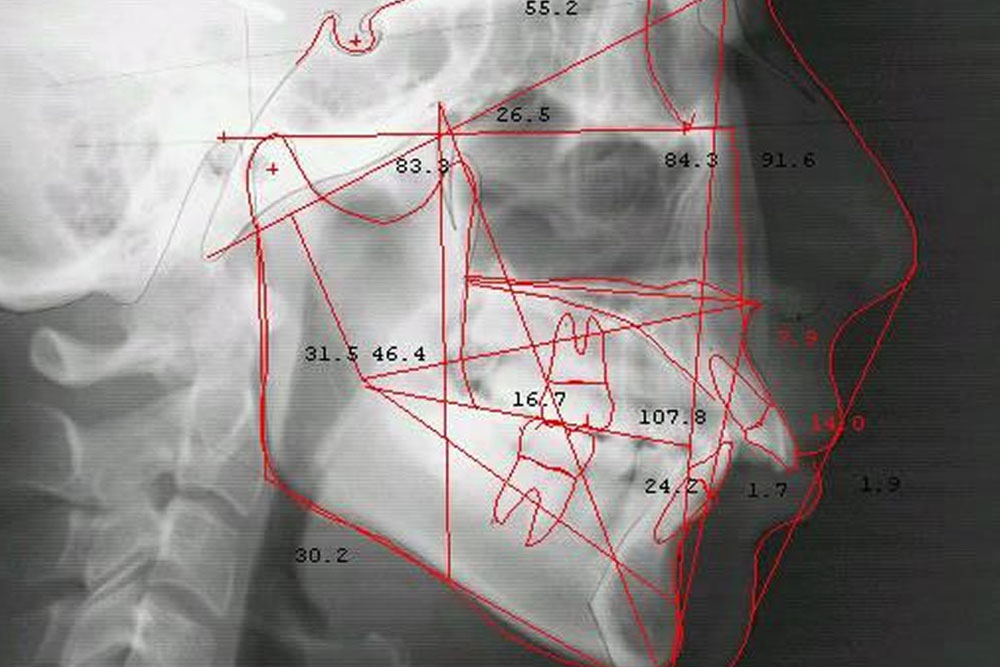

連携④ 日本矯正歯科学会専門医

歯列矯正や顎関節症などの咬みあわせの治療では、セフィロレントゲンなどの機器を使用し、適切な診断を基に日本矯正歯科学会認定医が的確な治療を実施。矯正中に虫歯などの治療が必要な患者様は担当医(歯科医)が処置を行い、連携を行いながら治療を進めていきます。日本矯正歯科学会の認定医による治療をご希望の方は、ご予約の際お申し付け下さい。

セファロレントゲン

歯列矯正や咬みあわせの治療を始める際に、顔の骨格など調べるために必要な機器です。高精度な矯正治療には必須の矯正専用のレントゲンです。